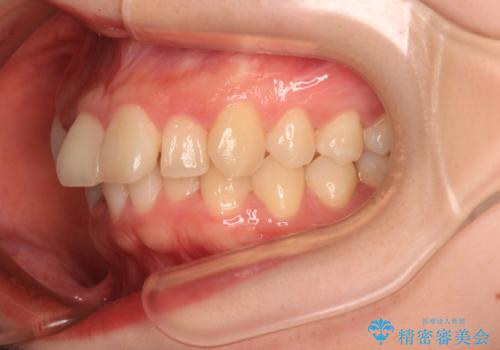

- 上下前歯のデコボコを気にして来院された患者様です。

マウスピースでもワイヤー装置でも対応可能でしたが、右側の咬み合わせが上顎がやや前方に位置していることから、補助装置を使用することが推奨されました。

右上と左下の第一大臼歯2本が周辺の歯と比べて位置がずれていたため、ゴムかけやワイヤーに曲げを入れることで移動を試みましたが、どうよら癒着をしており、移動困難と判断されました。

見た目や咬み合わせに違和感がないとのことで、癒着歯の無理な移動は試みずに治療を終えることとしました。